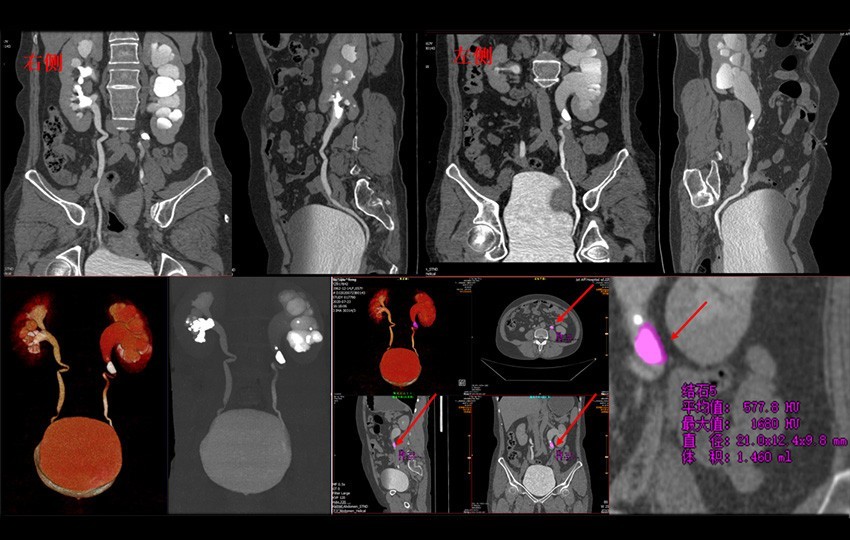

Clinical Gallery